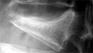

BKP手術

骨セメント注入療法

2)X線圧迫骨折の定義:左から2番の脊椎X線像で、B/A=80%以下、C/A=75%以下が圧迫骨折。圧迫骨折=高度の骨粗鬆症を意味します。

正常脊椎X線

高度圧迫骨折